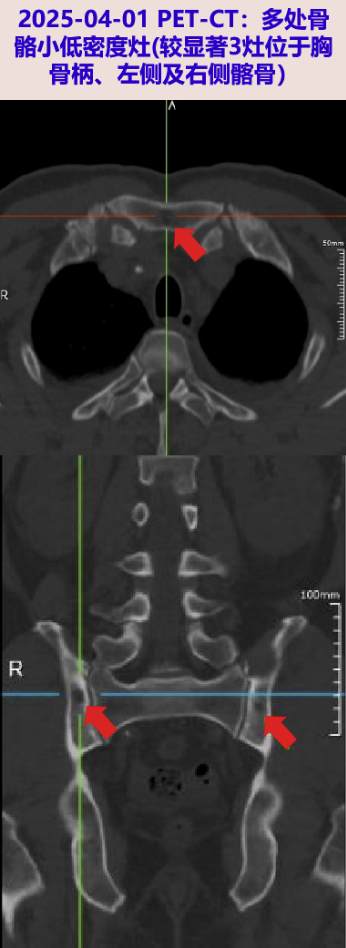

2025-04-01 血mNGS回报阴性;完善PET/CT:1.两肺炎症,双侧胸腔积液伴两肺下叶部分膨胀不全,心包少量积液;2.骨髓增生性改变,多处骨骼小低密度灶,请结合临床除外MM累及;3.脾脏糖代谢增高,考虑与发热相关;左侧肾上腺良性病变;腹盆腔腹膜增厚;盆腔少量积液。

患者老年男性,发热伴贫血,免疫固定电泳阳性(IgG-k M带),血游离轻链KAPPA升高,PET-CT示多处骨骼小低密度灶,骨髓活检病理示浆细胞数目稍增多,约占骨髓有核细胞的15%,增生浆细胞Kappa呈轻链限制性表达,为浆细胞克隆性增生,DRD方案治疗后无发热,故诊断明确。